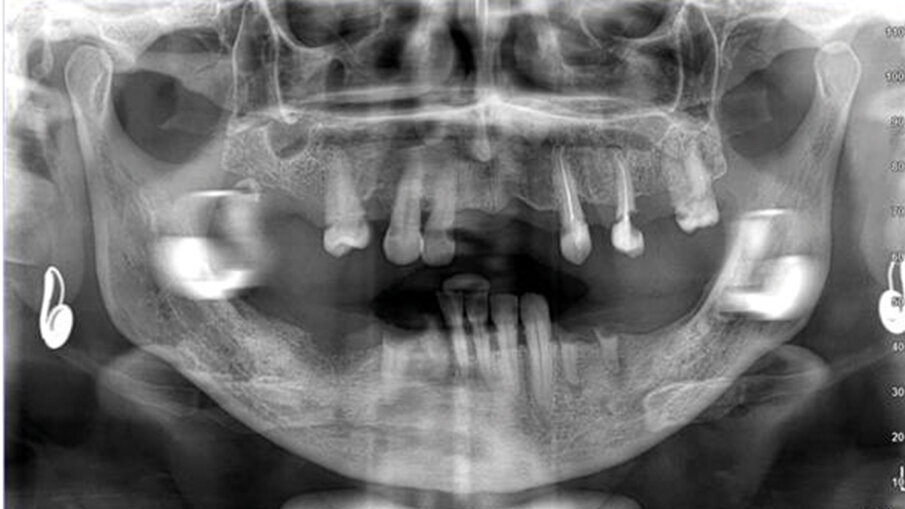

La paziente, una donna di 69 anni in buono stato di salute generale e senza terapie farmacologiche in corso, presentava una condizione orale fortemente compromessa caratterizzata da molte estrazioni dentali pregresse, una dentatura residua gravemente danneggiata da carie distruttive e numerosi processi infiammatori apicali e periapicali, che comportavano una severa mobilità della maggior parte dei denti presenti (Figg. 1, 2). La paziente utilizzava già una protesi parziale mobile superiore, la quale aveva causato nel corso degli anni un’ampia area di decubito palatale (Fig. 3). Data la compromissione estetica e funzionale dell’intero apparato masticatorio, si è deciso di procedere con una riabilitazione mediante una protesi avvitata supportata da impianti.

Il presente case report illustra le potenzialità dei flussi digitali e della chirurgia guidata nella riabilitazione implantoprotesica a carico immediato. Necessitando di riabilitare sia l’arcata superiore che inferiore, in accordo con la paziente si è deciso di suddividere il trattamento in due fasi chirurgiche separate, concentrandosi in questo articolo sull’arcata superiore.